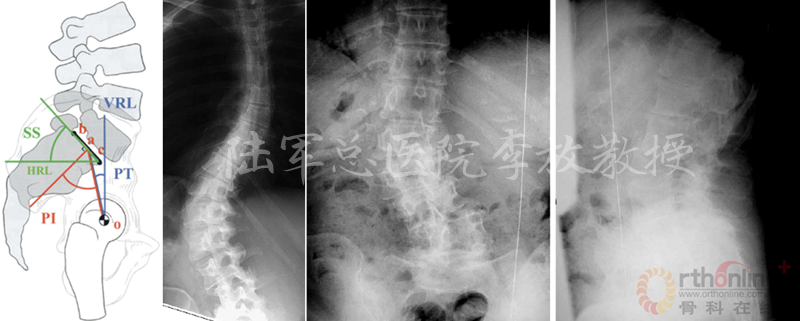

在微创脊柱外科热潮汹涌而至的当下,腰椎退变性疾病的治疗快要达到“无微不至”的程度。那么,就脊柱领域难度超高、风险性巨大的退变性脊柱侧凸而言,医生如何选择开放或微创技术,成为目前脊柱外科的热点之一。

陆军总医院、全军骨科研究所李放教授分析了国内外相关研究,并结合临床经验得出结论:开放手术能够获得更好的矫形和减压效果;微创技术作为脊柱医生手中的新武器,对于一部分畸形较轻的病例,微创技术可以发挥其优势,但要严防特殊并发症;对于畸形严重的病例,微创手术处理存在困难,可谓开放能及微创所不及。他认为,开放和微创技术应该有机结合,重要的是如何去选择适应证,对不同的病例制订个体化方案。